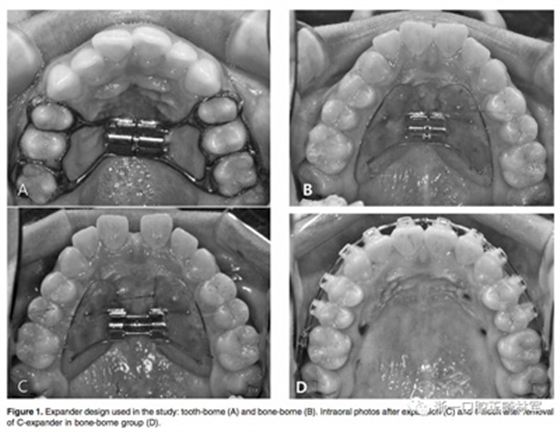

牙支持式快擴的帶環(huán)設在第一前磨牙和第一磨牙上,見Figure 1A。骨支持式快擴見Figure 1B-D,由直徑1.8毫米,長8.5毫米的四個微種植釘支撐,兩個位于尖牙與第一前磨牙之間,另外兩個位于第二前磨牙與第一磨牙之間的腭部牙槽骨中。 每天轉動1/4圈(0.25毫米)。